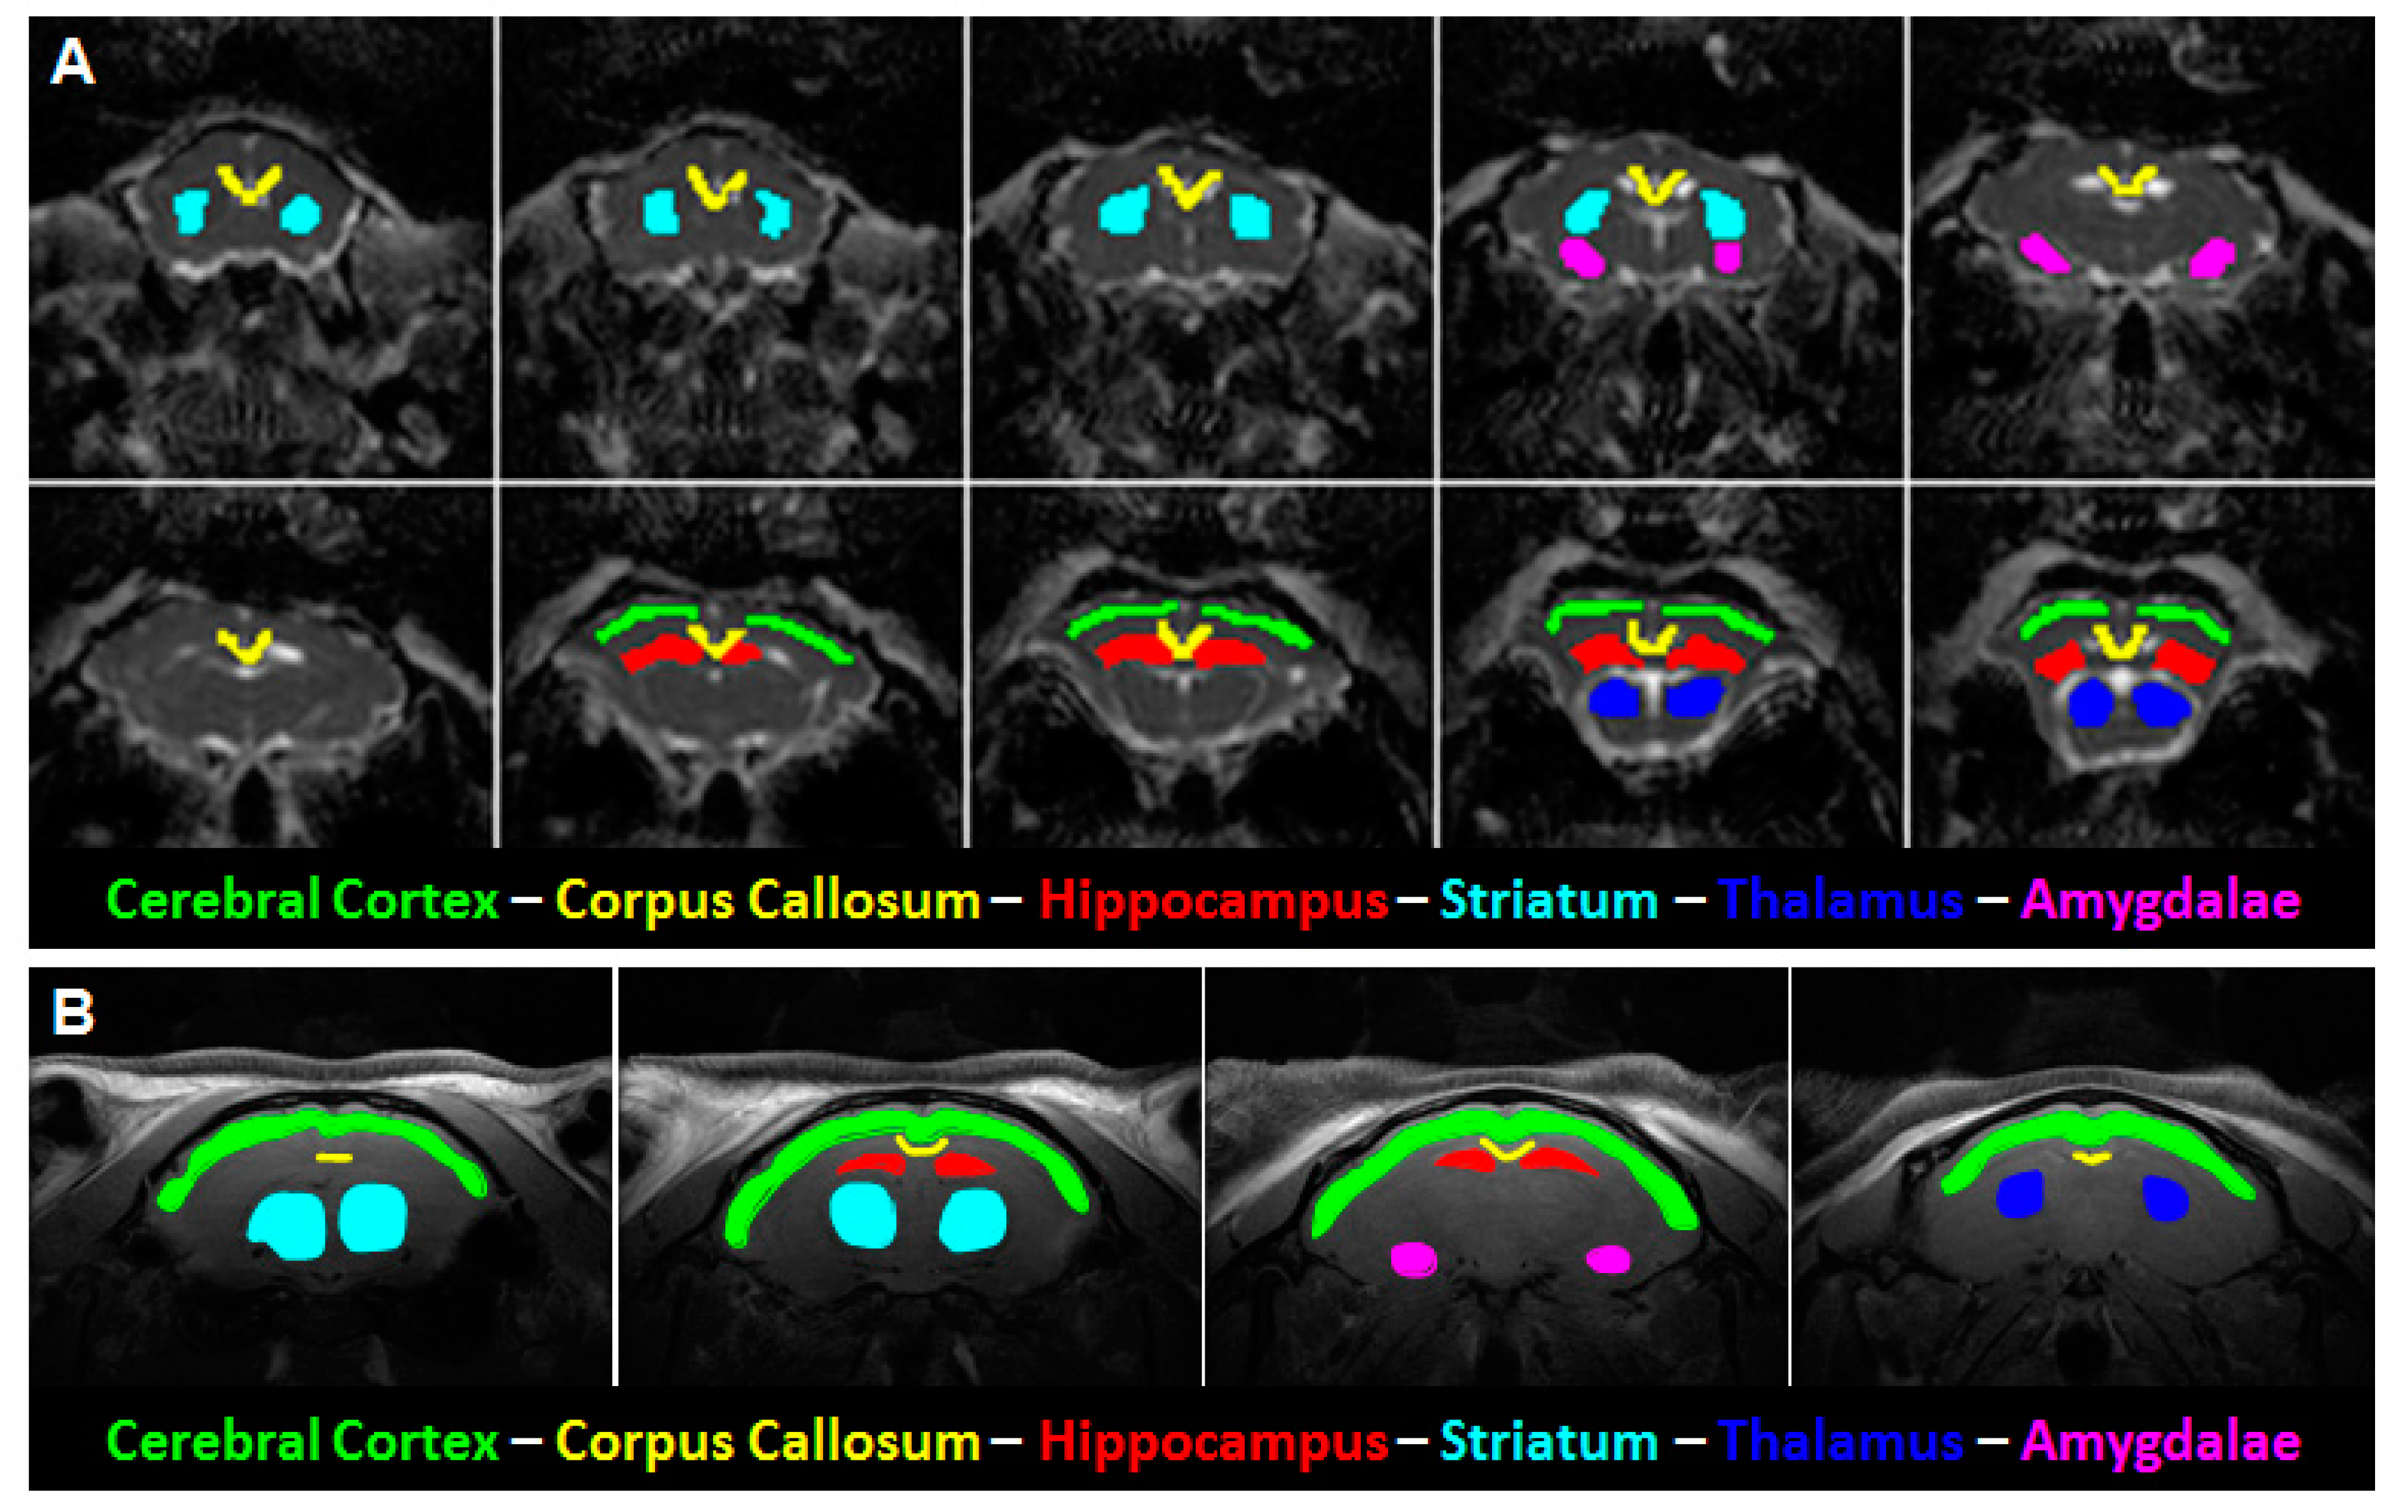

2.2. In Vivo MRI

2.3. Data Processing